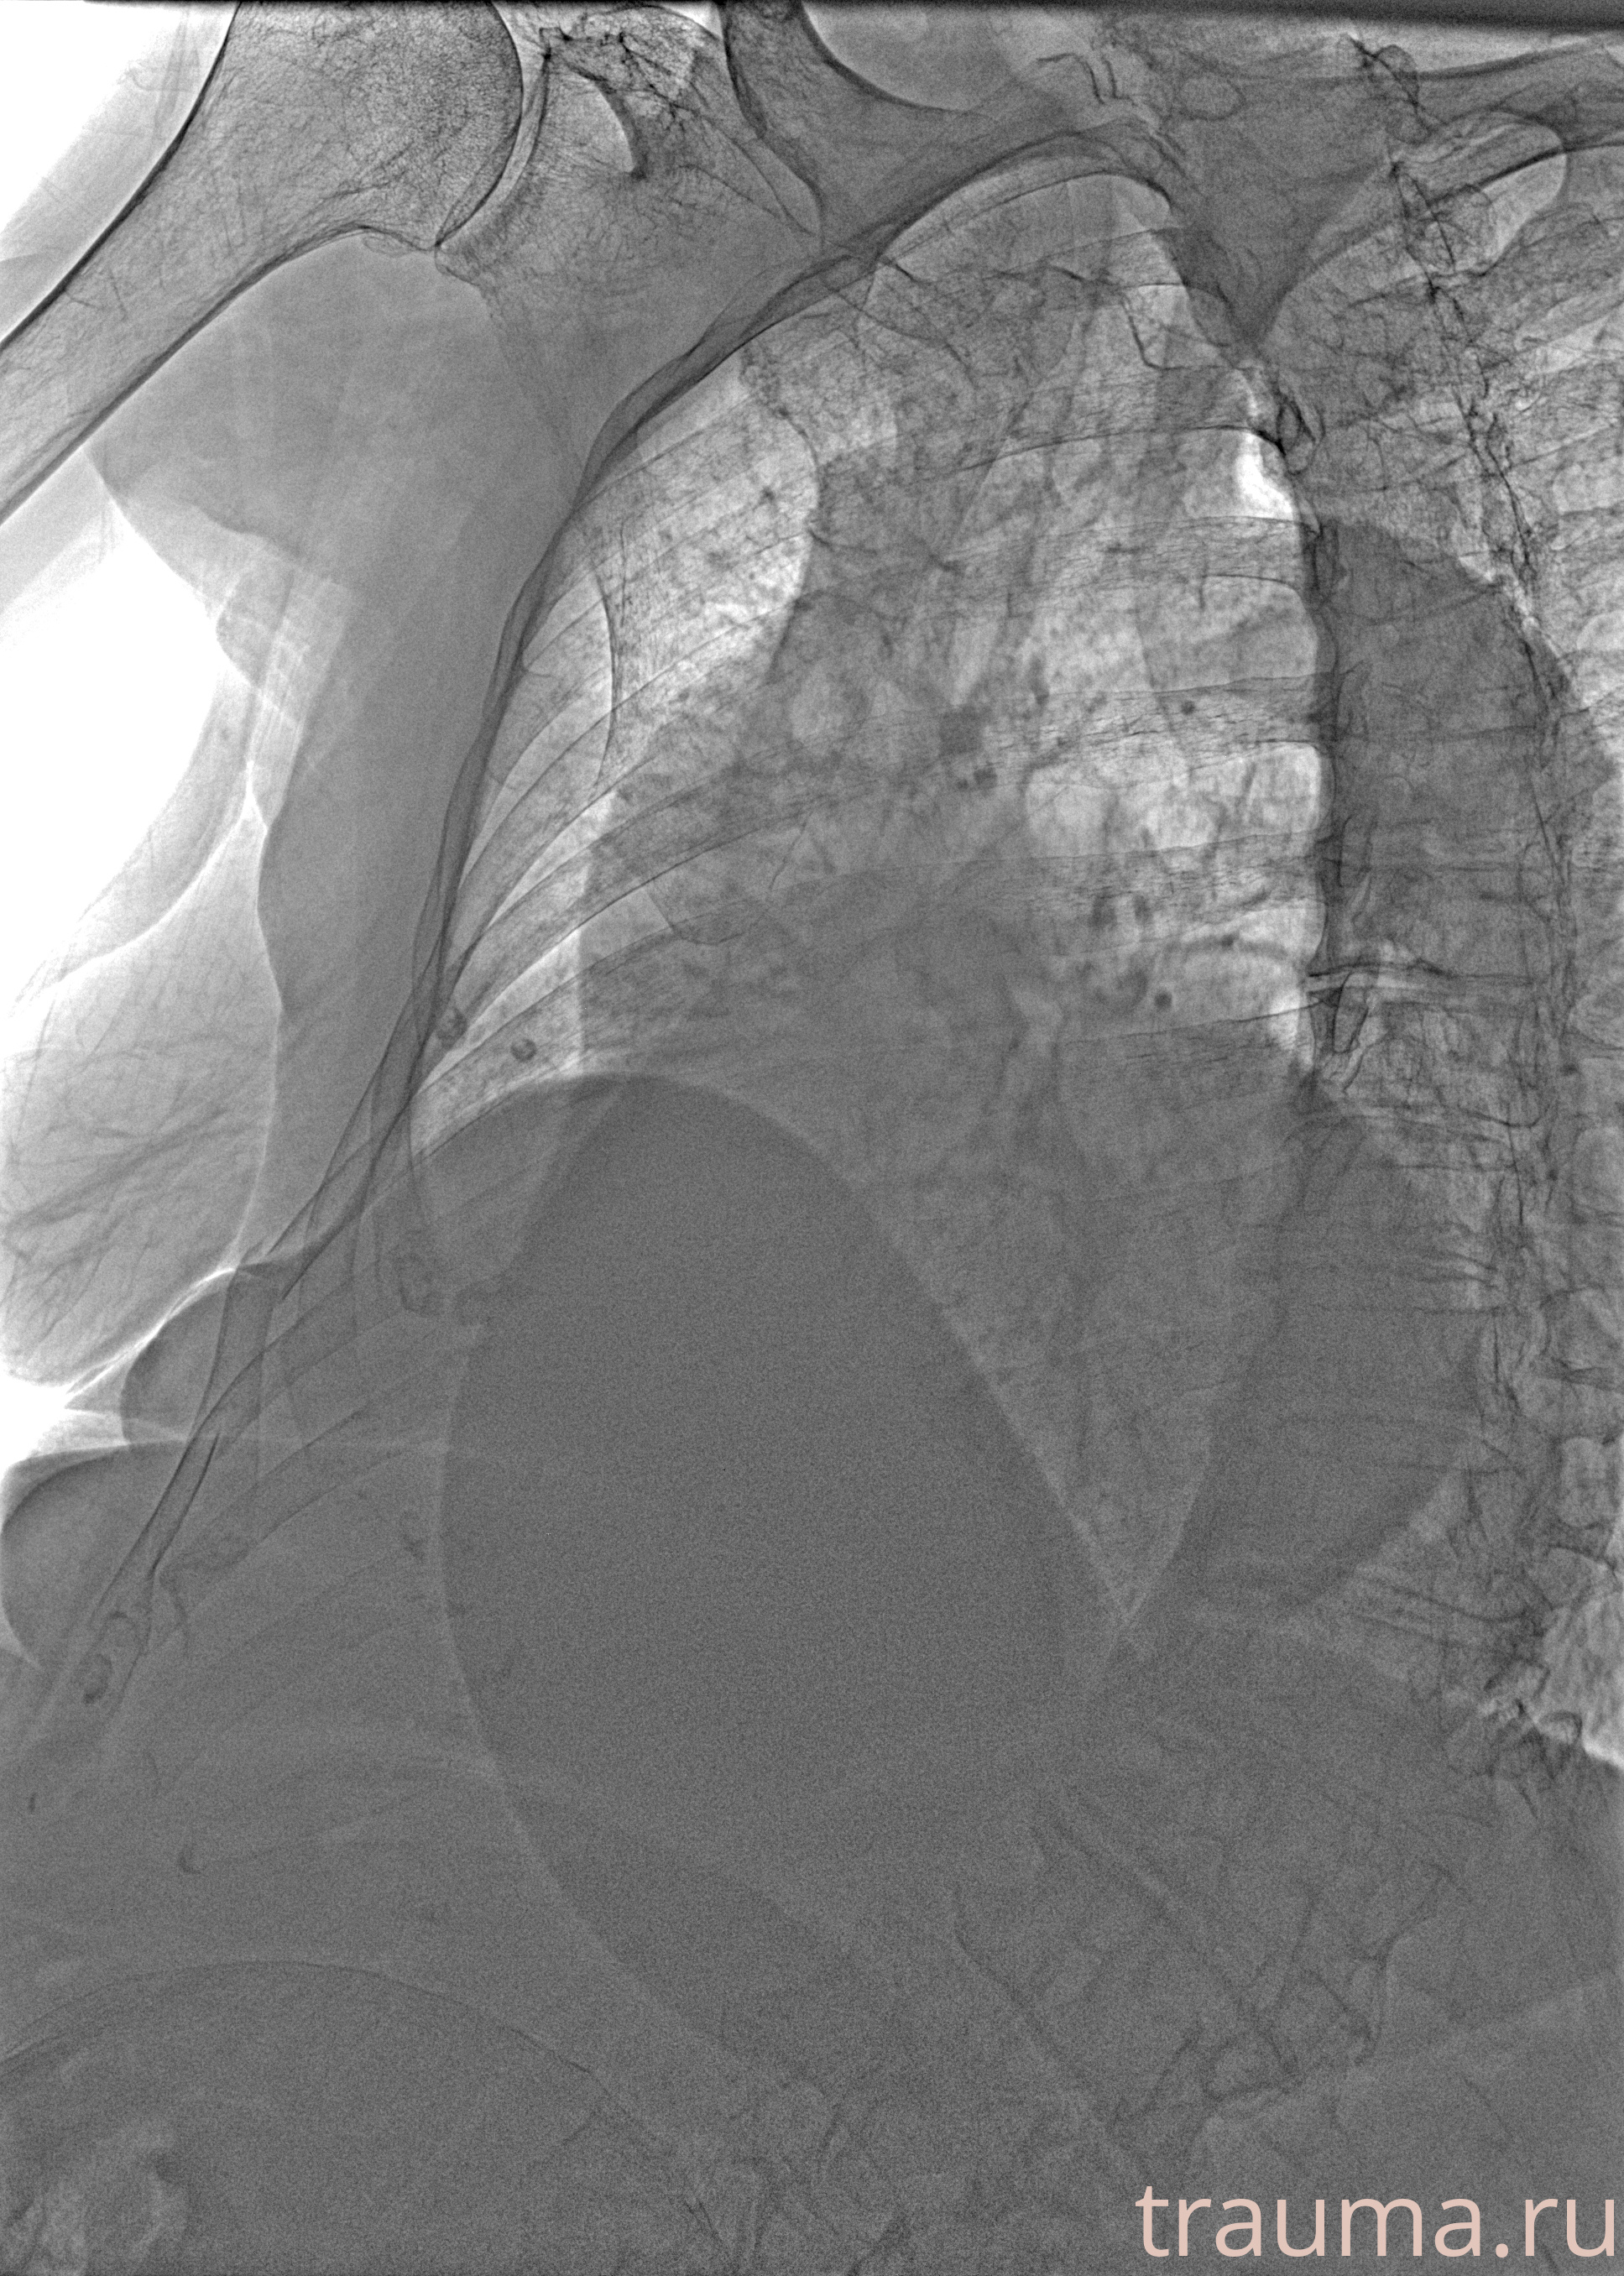

Рентген на дому: по вашему адресу приезжает врач-рентгенолог, травматолог-ортопед с мобильным рентгеновским аппаратом, проводит диагностику травмы или заболевания, делает необходимые рентгенограммы, дает рекомендации по дальнейшему лечению. Получить качественные снимки в домашних условиях возможно благодаря уникальной методике, разработанной МосРентген Центром для института  Склифосовского

при переломе шейки бедра и пневмонии от компании МосРентген Центр - партнера Института имени Склифосовского